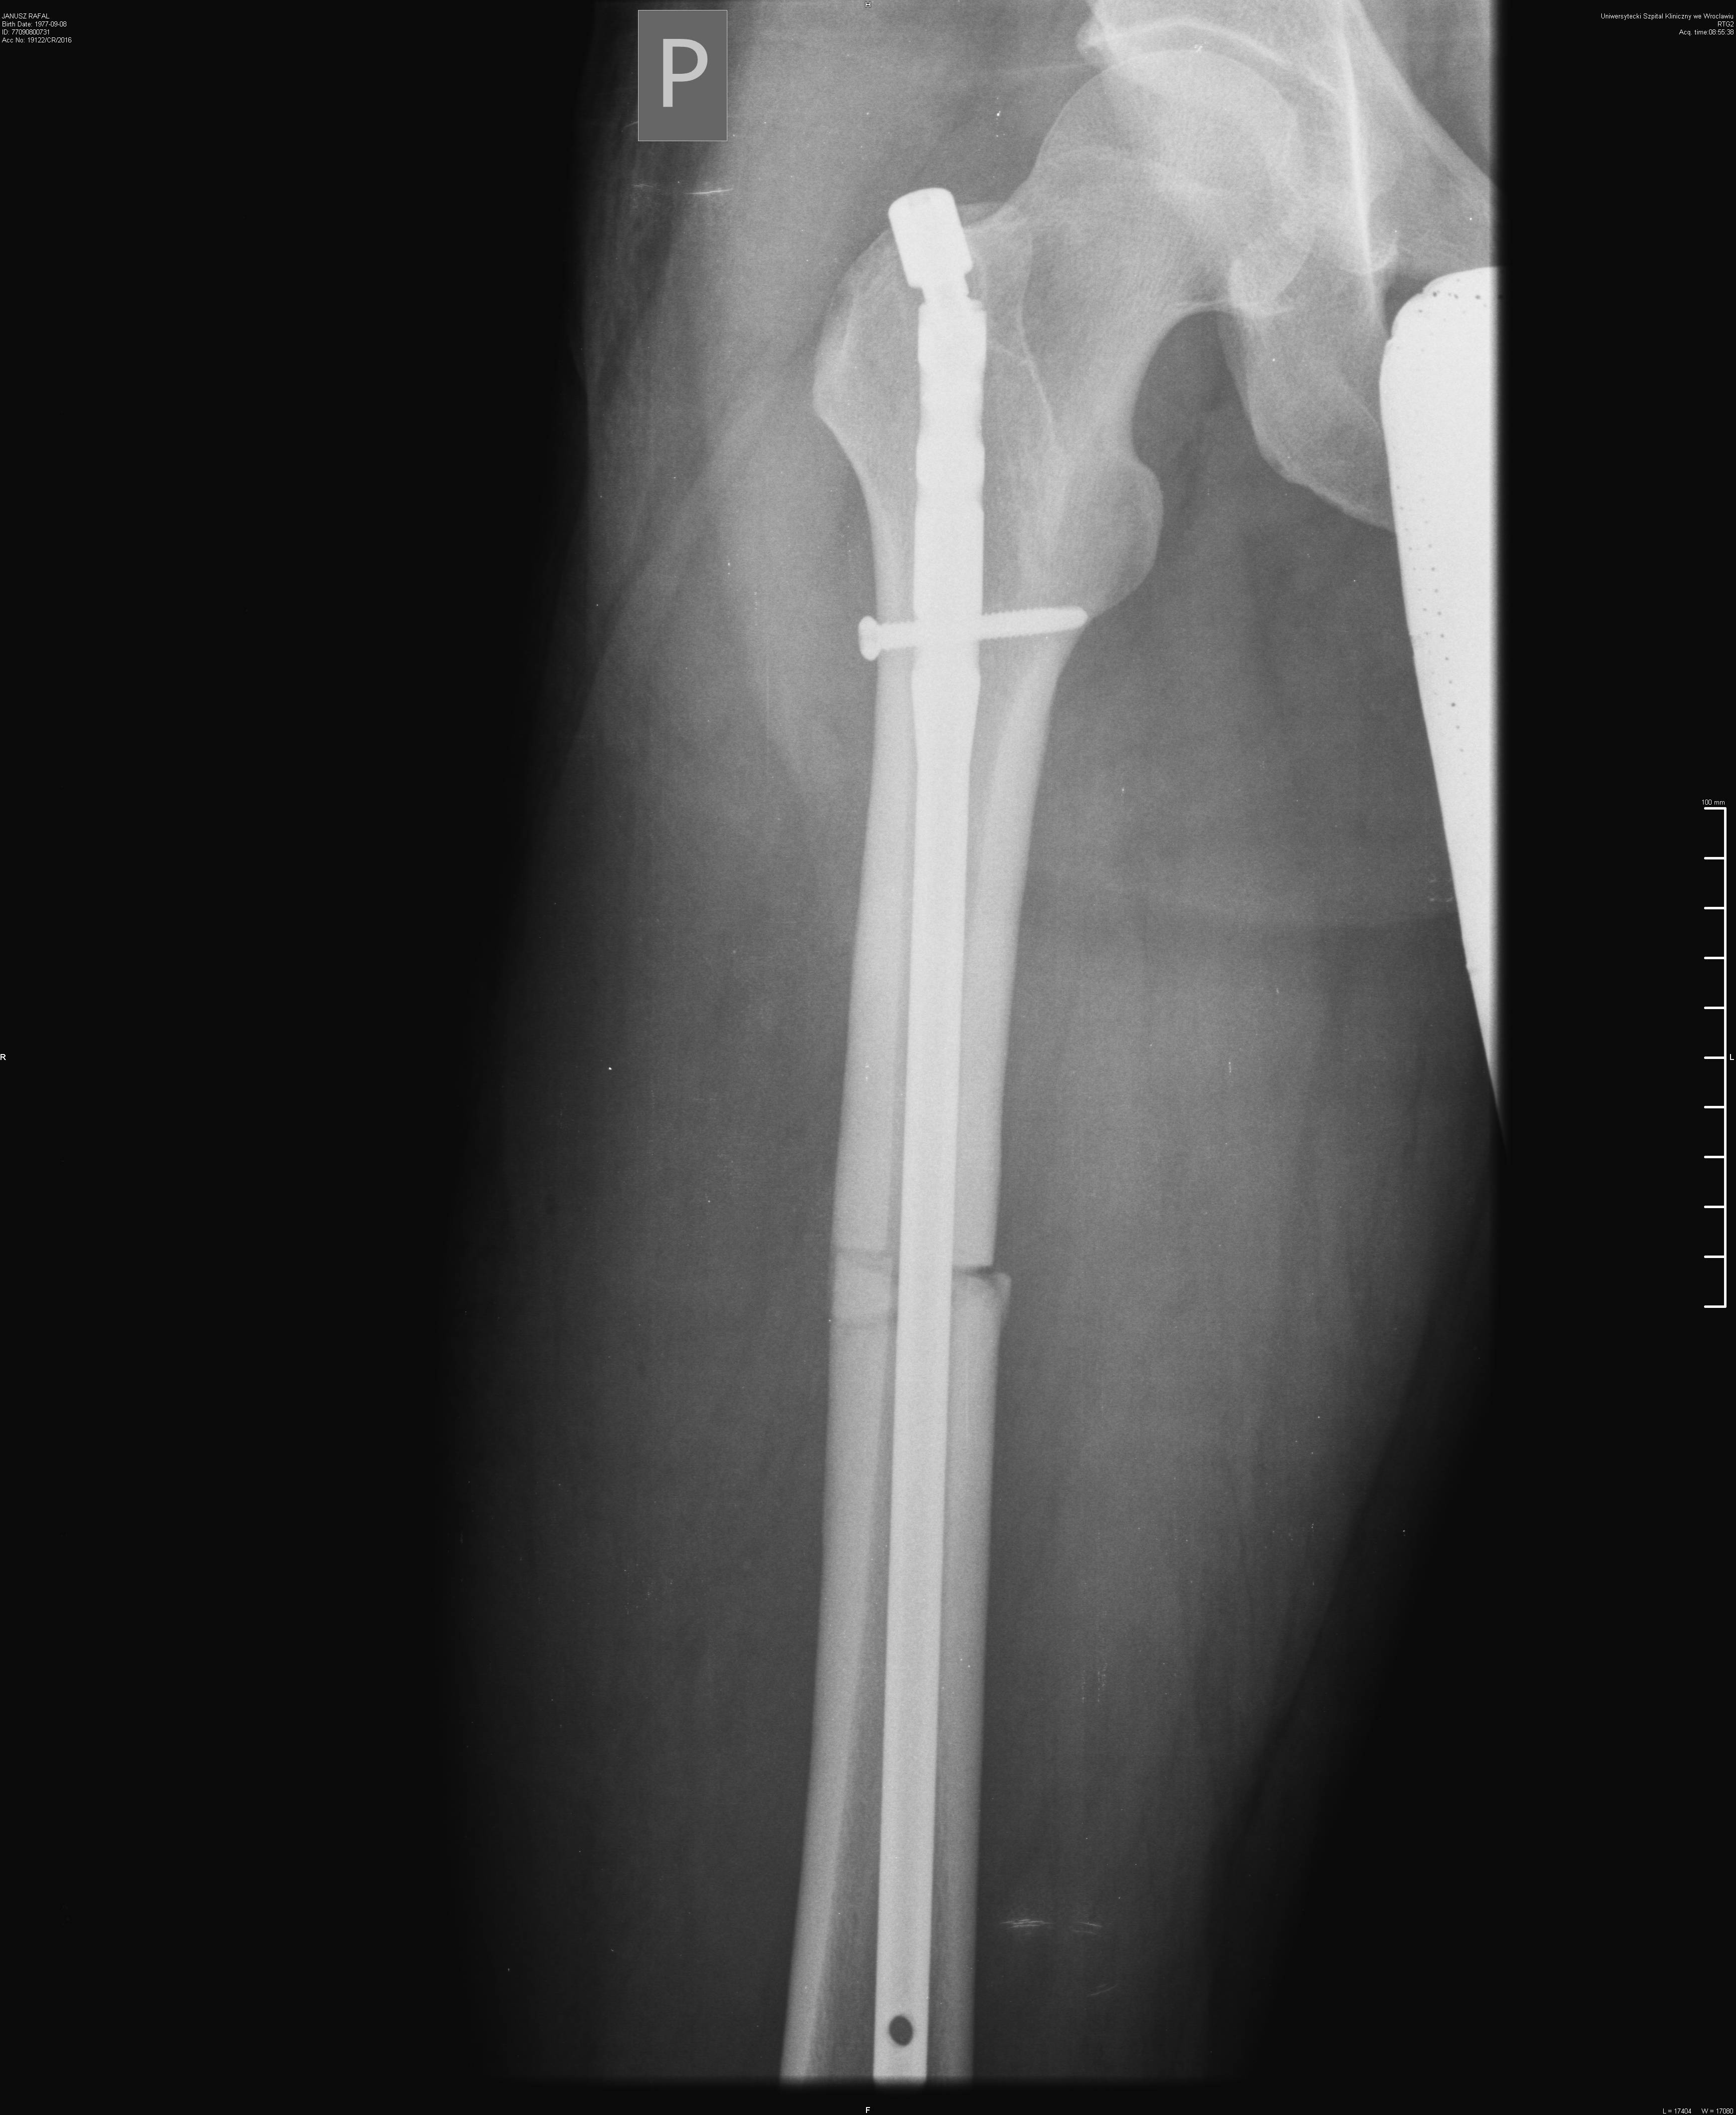

Wklejam bo może ktoś jeszcze nie miał nic złamanego i jest ciekawy jak to wygląda.

Terminator Rafał . Ale widzę że już się zrasta.

Bramki na lotnisku będą ci teraz piszczały

Swoją drogą to już gipsu się nie używa?